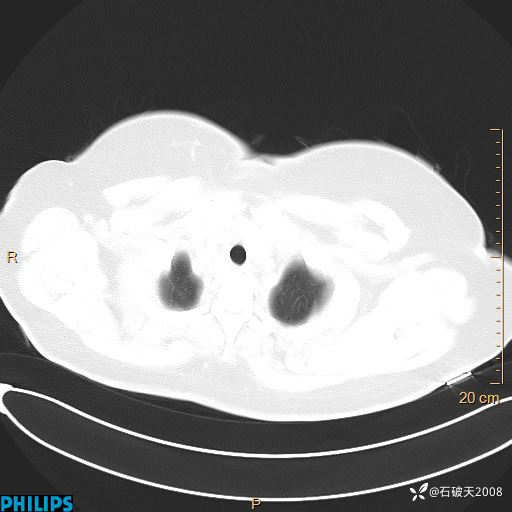

肺结节病?纵膈型肺癌?淋巴瘤?有点意思,欢迎围观

女 52岁 主 诉:咳嗽10余天,咳痰2天。

现病史:10余天前无明显诱因出现咳嗽,呈阵发性干咳,伴咽喉部发痒,无咽痛,无咳痰,无鼻塞、流涕、打喷嚏,无发热、畏寒、寒颤,无头痛、头晕,无胸闷、胸痛,无反酸、烧心,无腹痛、腹泻,无尿频、尿急,无皮疹等,在当地诊所求治,给予口服药物治疗(具体不详),病情无好转。遂在当地社区卫生服务中心开具口服药物治疗(具体不详),疗效欠佳。2天前出现咳痰,在我院门诊求治,行胸部CT提示肺部感染,建议住院,患者要求口服药物治疗,目前仍咳嗽、咳白色粘痰,白天量多,夜间自觉喉部喘鸣音,遂再次来院就诊,以“肺部感染”为诊断收入院。发病以来,神志清,精神可,饮食可,夜间睡眠差,大小便正常,近期体重无明显变化。

肺窗